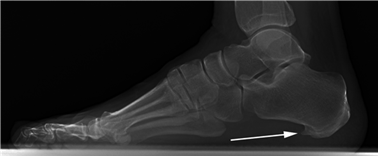

Weight-bearing anteroposterior (AP), lateral, and sesamoid axial radiographs are mandatory. On the AP view, the surgeon measures the Hallux Valgus Angle (HVA, normal < 15°), the Intermetatarsal Angle (IMA, normal < 9°), and the Distal Metatarsal Articular Angle (DMAA). The lateral view is scrutinized for Meary's angle (talo-first metatarsal angle) to identify midfoot collapse, as well as the presence of dorsal osteophytes indicative of hallux rigidus. The sesamoid axial view is critical for assessing the degree of sesamoid subluxation and the integrity of the crista.

Avascular necrosis of the metatarsal head is a devastating complication primarily associated with distal osteotomies. It presents with insidious onset of pain, swelling, and eventual radiographic collapse of the articular surface. Prevention is paramount and relies on preserving the plantar-lateral soft tissue attachments during the lateral release. If symptomatic AVN occurs and progresses to joint destruction, the definitive salvage procedure is a first MTP arthrodesis, often requiring structural bone grafting to restore metatarsal length.